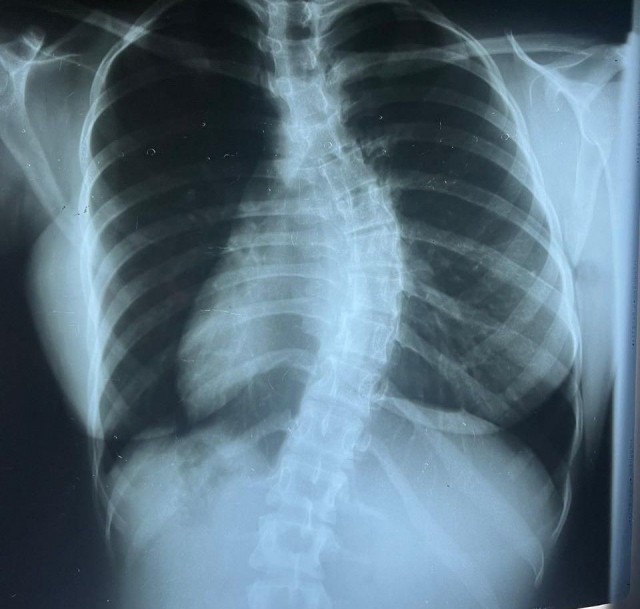

Feira de Santana Notícias 24h - Uma cirurgia inovadora de escoliose foi realizada no Hospital Geral Clériston Andrade (HGCA), em Feira de Santana, trazendo esperança e alívio para uma paciente de 17 anos que sofria com uma curvatura torácica grave da coluna.

A paciente, diagnosticada com uma escoliose classificada como Lenke 1 e progressiva, necessitava de intervenção cirúrgica urgente devido à evolução da curvatura e ao impacto na sua qualidade de vida. A cirurgia visou corrigir a deformidade, utilizando implantes e instrumentação para alinhar a coluna vertebral e proporcionar maior estabilidade. De acordo com os especialistas, o procedimento incluiu monitorização neurofisiológica, garantindo a preservação das funções neurológicas durante toda a operação.

Estima-se que, no Brasil, cerca de 2% a 4% da população desenvolvam escoliose, sendo mais comum em adolescentes do sexo feminino. Nos casos em que a curvatura ultrapassa os 40º, como ocorreu nesta paciente, a cirurgia passa a ser indicada, especialmente quando tratamentos conservadores, como fisioterapia e o uso de coletes, não apresentam resultados satisfatórios.